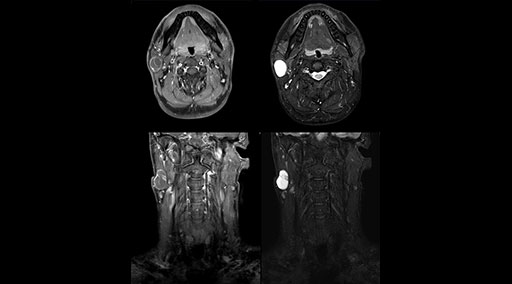

“Without using an endorectal coil we do our prostate MR at 0.5 mm resolution, following the European society of urology protocol [1]. For certain joints we use a virtual arthroscopy protocol with 1 mm pixel size and 2 mm slice thickness. Ingenia really excels in our neurography, brachial plexus and prostate scans. Our neurologists insist on using our 3.0T for those,” Dr. Kaakaji adds.

“Our DMG Lisle location includes a cancer center, so soft tissue neck scans, brachial plexus scans, and prostate scans are common. For these exams, mDIXON TSE provides excellent images with and without fat suppression all while helping us reduce repeats and work more efficiently,” Mr. Duffy says.

“With the 2-echo Philips mDIXON TSE the timing is short and the fatsat is very robust. The biggest thing is that you know your fat suppression will be good, even in thin patients or large patients that are off-center,” Mr. Sybesma says.

“mDIXON TSE raises our diagnostic confidence with its homogeneous

fat suppression. Neck exams and rheumatology patients are two examples where mDIXON TSE is especially useful,” Dr. Kaakaji says. “For us it’s also an efficiency boost in exams where we need pre and post T1-weighted images with great fat suppression.”